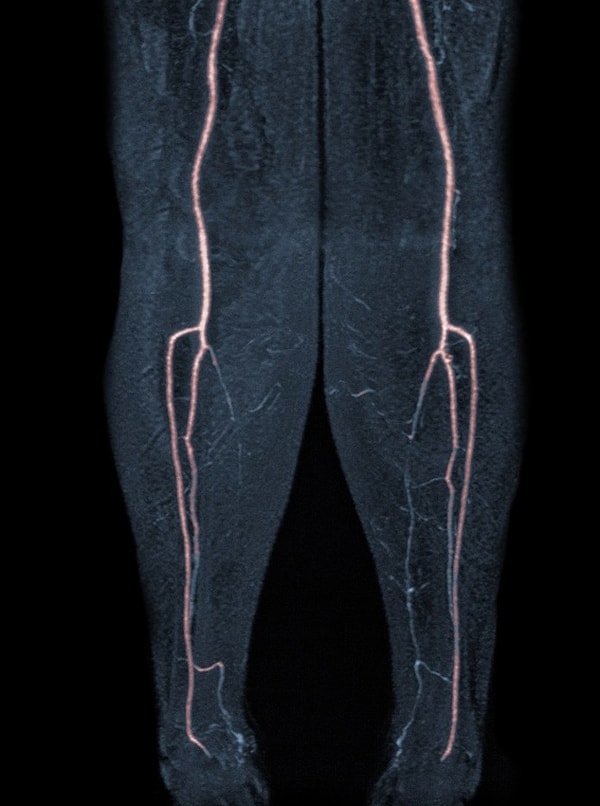

11. Sol bacaktaki damar tıkanıklıklarını gösteren bir görsel: